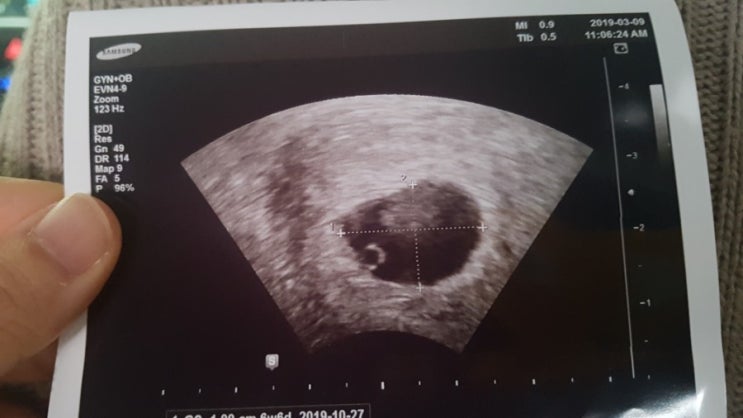

[태교일기]태아 초음파 사진첩 만들기

사진첩을 만들어 봅시당 https://coupa.ng/bjoFLP 접착식 앨범이라서 사진배열이 자유로워요 3월부터 10...

[임신일기]임신도 힘들다는 것을 왜 말해주는 사람이 없었을까?

6주 만에 알게 된 임신 임신을 알게된 건 올해 3월 7일 아직도 이 날짜를 잊지 못한다 평소 다낭성 난포증...